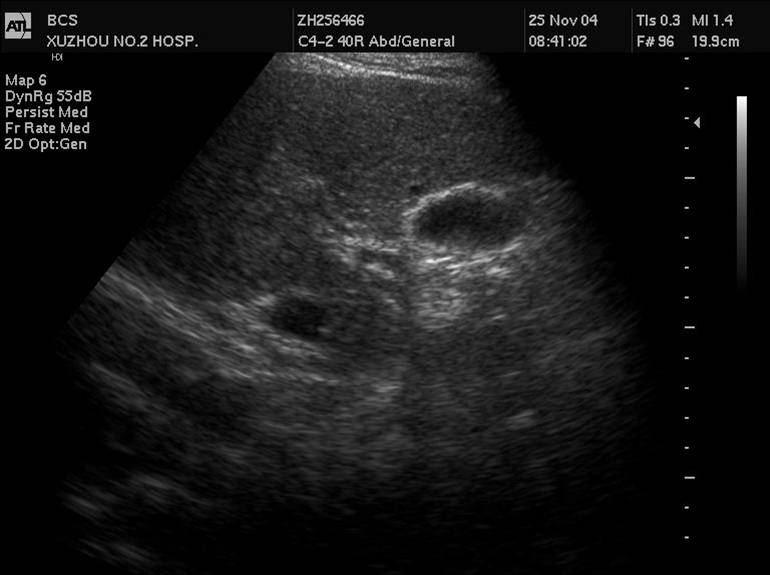

3 先天性胆管囊状扩张症